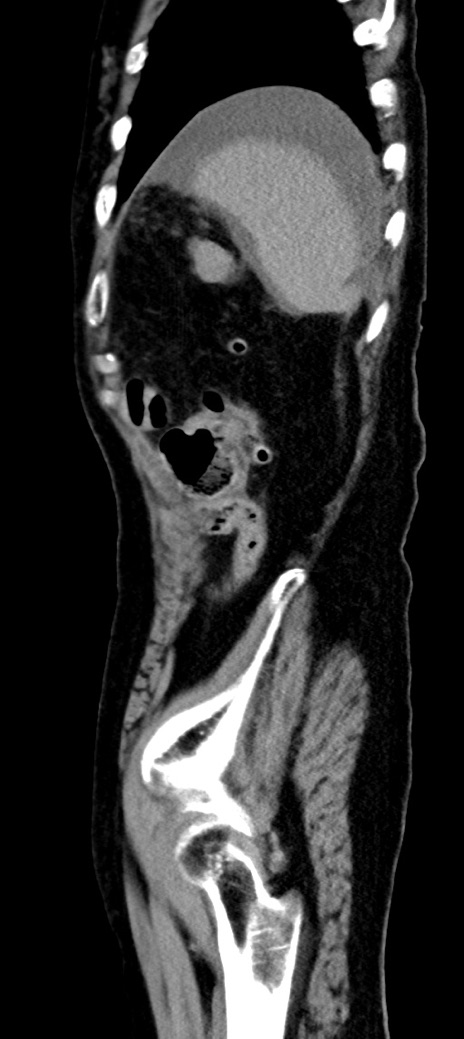

症例40(矢状断像)他院1日前

【症例】90歳代女性

【主訴】腹痛・嘔吐

【現病歴】 食欲低下、嘔吐があり昨日他院受診。肺炎と診断され入院となる。入院後より腹部全体に圧痛あり。胃管留置され経過みていたが、症状持続するため、

当院転院となる。

【既往歴】胸椎圧迫骨折、胆石症

【身体所見】腹部:中央に激痛あり、圧痛あり、反跳痛不明

【データ】WBC 17100、CRP 18.82